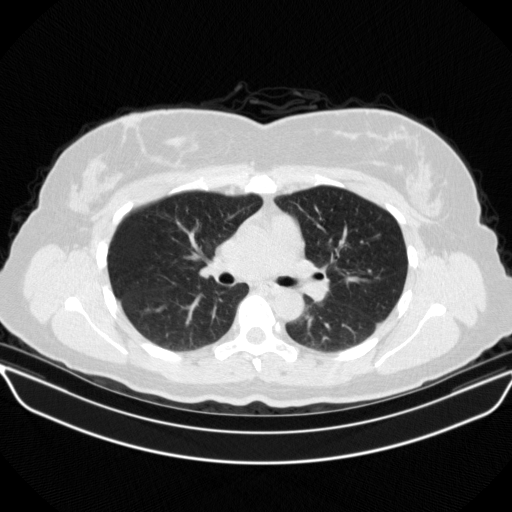

Reconstructed NATIVE CT scan (cycle consistency)

Full window (WL 1023.5, WW 4095 β†’ Low βˆ’1024, High +3071)

Lung window (WL -600, WW 1500 β†’ Low βˆ’1350, High +150)

Mediastinum window (WL 40, WW 400 β†’ Low βˆ’160, High +240)